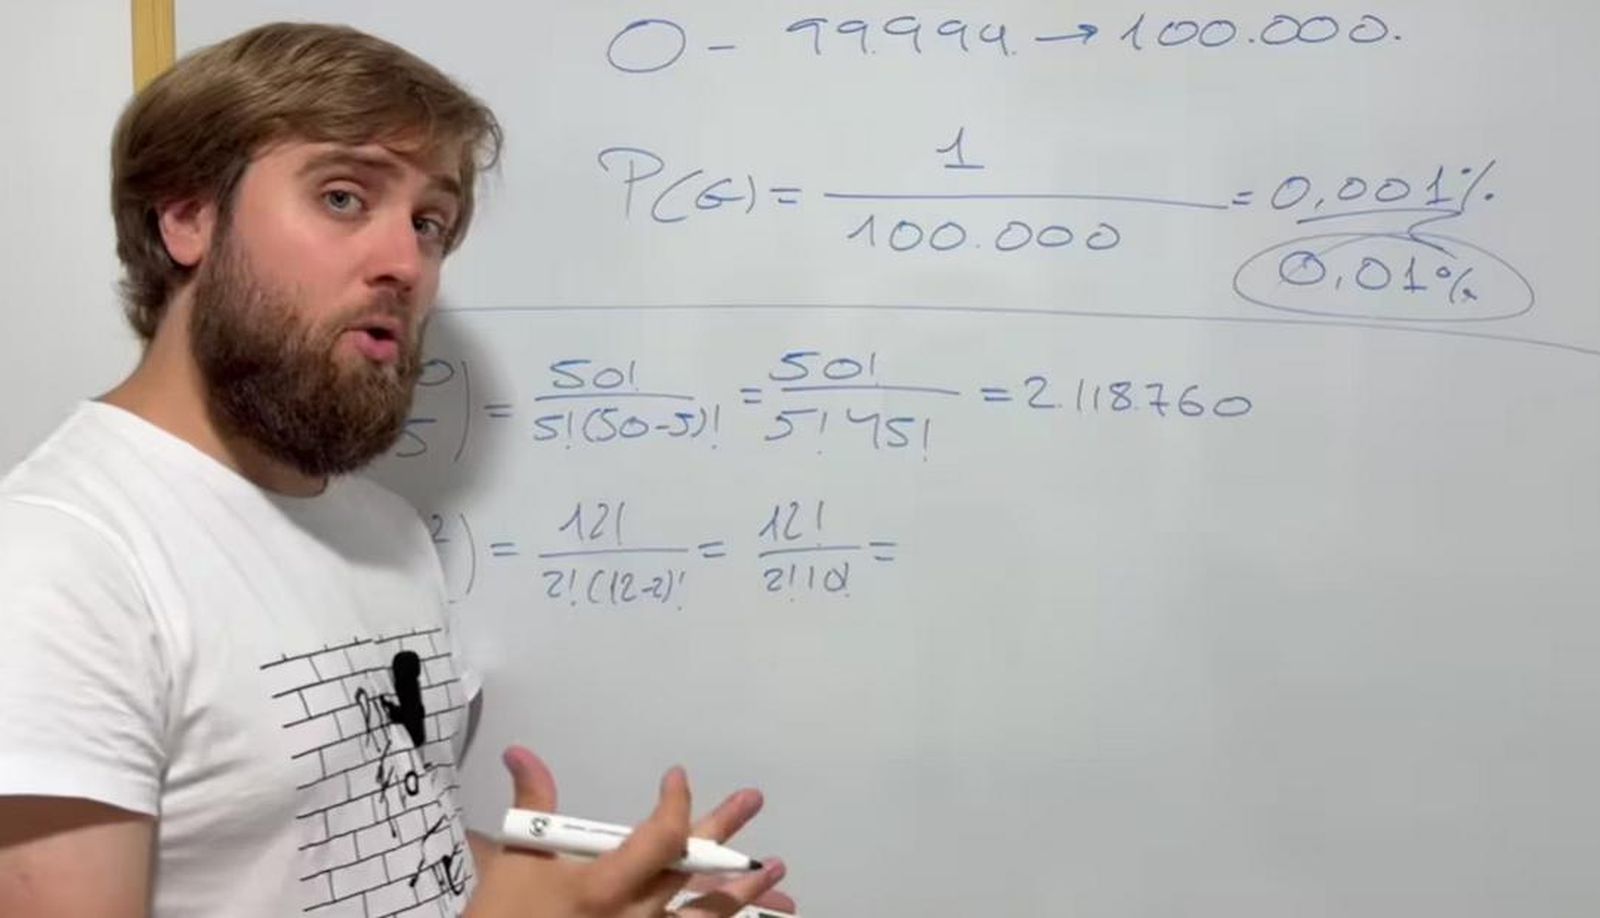

El Dr. Juan José López Galián, jefe de Servicio de Ginecología y Obstetricia del Hospital Quirónsalud San José, señala que la incidencia de placenta ácreta en España ha aumentado en las últimas décadas, alcanzando aproximadamente 1 caso por cada 530 partos. Este incremento se atribuye a factores de riesgo como cesáreas previas, placenta previa, cirugías uterinas, legrados endometriales y edad materna avanzada.

"El diagnóstico precoz es crucial", enfatiza el Dr. López Galián. "En casos de alto riesgo, se recomienda una ecografía específica para confirmar o descartar la placenta adherida". Esta ecografía es especialmente importante en pacientes con cesáreas previas, placenta previa o lesiones uterinas.

El momento ideal para realizar la ecografía es entre las semanas 18 y 24 de gestación, aunque en algunos casos se puede realizar en el primer trimestre. Si la ecografía no es concluyente, se recomienda una resonancia magnética.